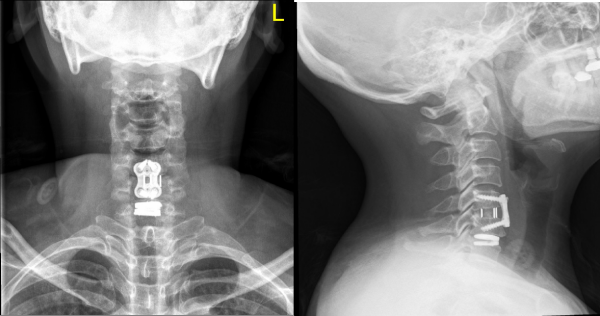

手术中,团队在显微镜下精准操作,仅通过100px的微创切口,成功摘除病变椎间盘,并植入适配的人工颈椎间盘假体。术后即刻解除神经压迫。术后第1天,患者颈肩疼痛、下肢无力状明显缓解;术后第2天顺利下床活动,经影像学检查确认假体位置精准、稳定性良好,目前已康复出院。

术后正侧位X线